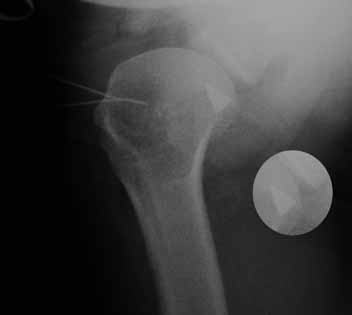

Больная В. 41 год. Во время выполнения операции Розенштейна – пересечение сухожилия двуглавой мышцы плеча

(транспозиции сухожилия двуглавой мышцы плеча, с проведением ёё под ротаторами плеча, к клювовидному отростку) произошел перелом конца съёмного лезвия скальпеля (Фирма: TRO-Microcut. №21; Lot 21/889-01 Exp: 2013-02).

После нескольких безуспешных попыток поиска операция закончена, рана зашита. Послеоперационный период гладкий.

Предыдущий опыт использования лезвий «Paragon» давало шанс врачу: лезвия не кололись, а вначале деформировались, либо частично ломались. В данном случае очень хрупкое лезвие, во время работы в ограниченном пространстве, обломилось с «отстреливанием» отломка.